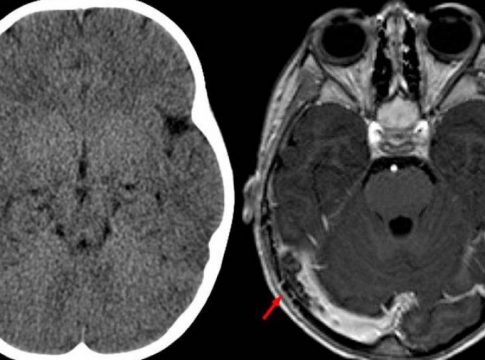

La TC cerebral simple solo identifica las anomalías encontradas en la TVC alrededor del 30% de las veces. El principal hallazgo en la TC simple es una hiperdensidad de una vena cortical o seno dural con posibles signos secundarios o indirectos como hemorragia o edema.